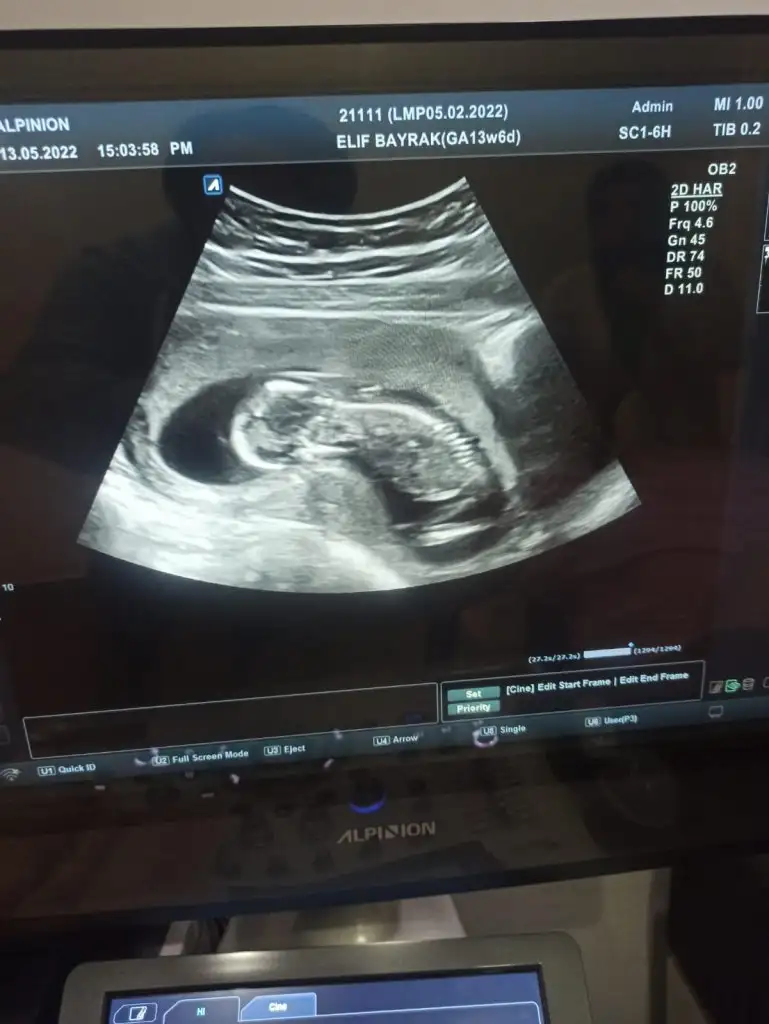

Bu erkek oluyor galiba değil mi ?12+1 çıktı

Nuba göre bakılmıyor mu bu haftalarda bilmiyorum kiBu erkek oluyor galiba değil mi ?

Kiz olunca üç çizgi oluyormus bunda 2 var sanki

prenses gibi12+1 çıktı